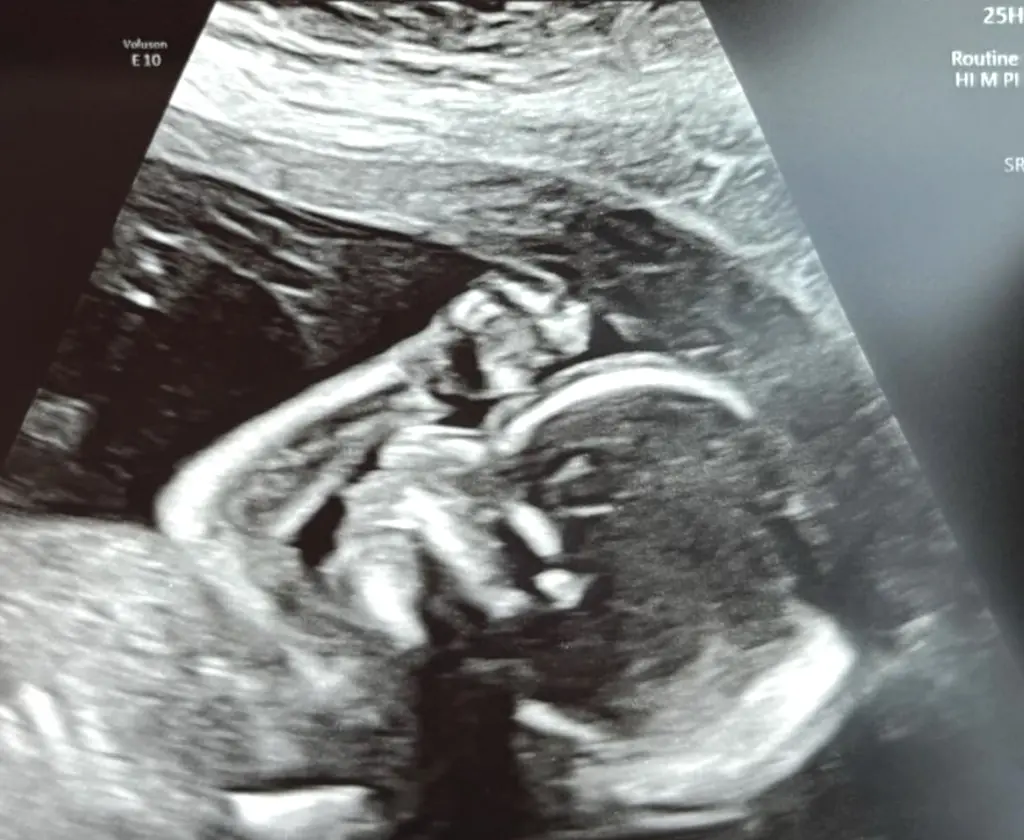

On Tuesday, Blanchard shared a sonogram image from her 20-week checkup on social media.

However, there was one detail that left some fans concerned.

Some were quick to point out that she had not blurred out the name of her OBGYN (a doctor of obstetrics and gynecology), raising concerns about her privacy.

One user commented: "Thank god the date is on there so everyone can stop claiming different dates for you/saying you’re making this up!"